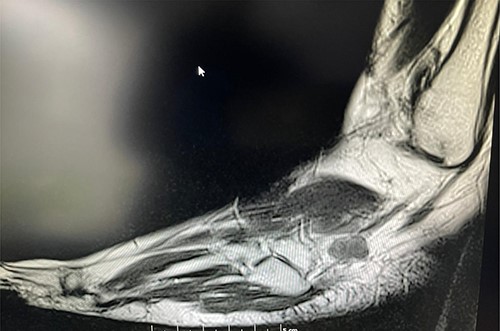

A 50-year-old lady presented to us with a lump in her left foot on the lateral aspect at the level of the calcaneocuboid joint for a 1-year duration, which was associated with pain. She consulted her GP who advised an US scan. This revealed a lump over the dorsum of the left foot on the lateral side. She also had a magnetic resonance imaging (MRI) scan which was indeterminate (Figs 3 and 4). It was reported as a suspected sarcoma. She was then referred to the Sheffield sarcoma unit where she underwent a biopsy of the swelling; which was reported as angiomyolipoma (a benign swelling). She was not keen on excision initially, but as the swelling increased in size and started becoming painful, she underwent an excision of the lesion under our care and the histopathologic examination of the excised sample confirmed it to be angioleiomyoma. The post-operative period was uneventful and she was discharged from our care after 10 weeks. At this time, she was symptom-free and had a pain score of 0/10.

T2 axial MRI image of the soft tissue lesion over the lateral foot in Patient 2 showing a lesion which is heterogeneous and slightly hyperintense to the muscle.

Similarly, in Case 2, the patient had an MRI scan which reported an indeterminate swelling suggestive of a possible sarcoma. As the MRI findings were not characteristic of the MRI findings of an angioleiomyoma, such as T1: isointense or hyperintense to muscle, T2: heterogeneous and slightly hyperintense to muscle and T1 C+ (Gd): homogenous to heterogeneous enhancement, suspicion of the sarcoma was reported from the MRI scan findings and referral to sarcoma unit was advised. This clearly shows that the US and the MRI scan findings can suggest a different diagnosis, and a confirmed diagnosis was only established following excision and histopathological examination of the excised lesion. Usually, angioleiomyomas have a peripheral low-intensity signal rim corresponding to a fibrous pseudo capsule with adjacent vascular structures with isointense or hypointense to muscle on T1 images and heterogeneous and slightly hyperintense to muscle on T2 images.